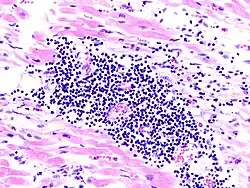

- Citocinas. Las citocinas que participan en la fisiopatología de la insuficiencia cardíaca incluyen el factor de necrosis tumoral alfa, Interleucina-1, Interleucina-6, la serotonina, prostaciclina, bradicinina y tromboxano, que liderizan la respuesta inflamatoria de la IC.[14][15] Las citocinas producen remodelación ventricular, anormalidades del metabolismo (anorexia y caquexia), desacople del receptor β de la adenilciclasa, disminuye el inotropismo (regulación contráctil) cardíaco e induce apoptosis.